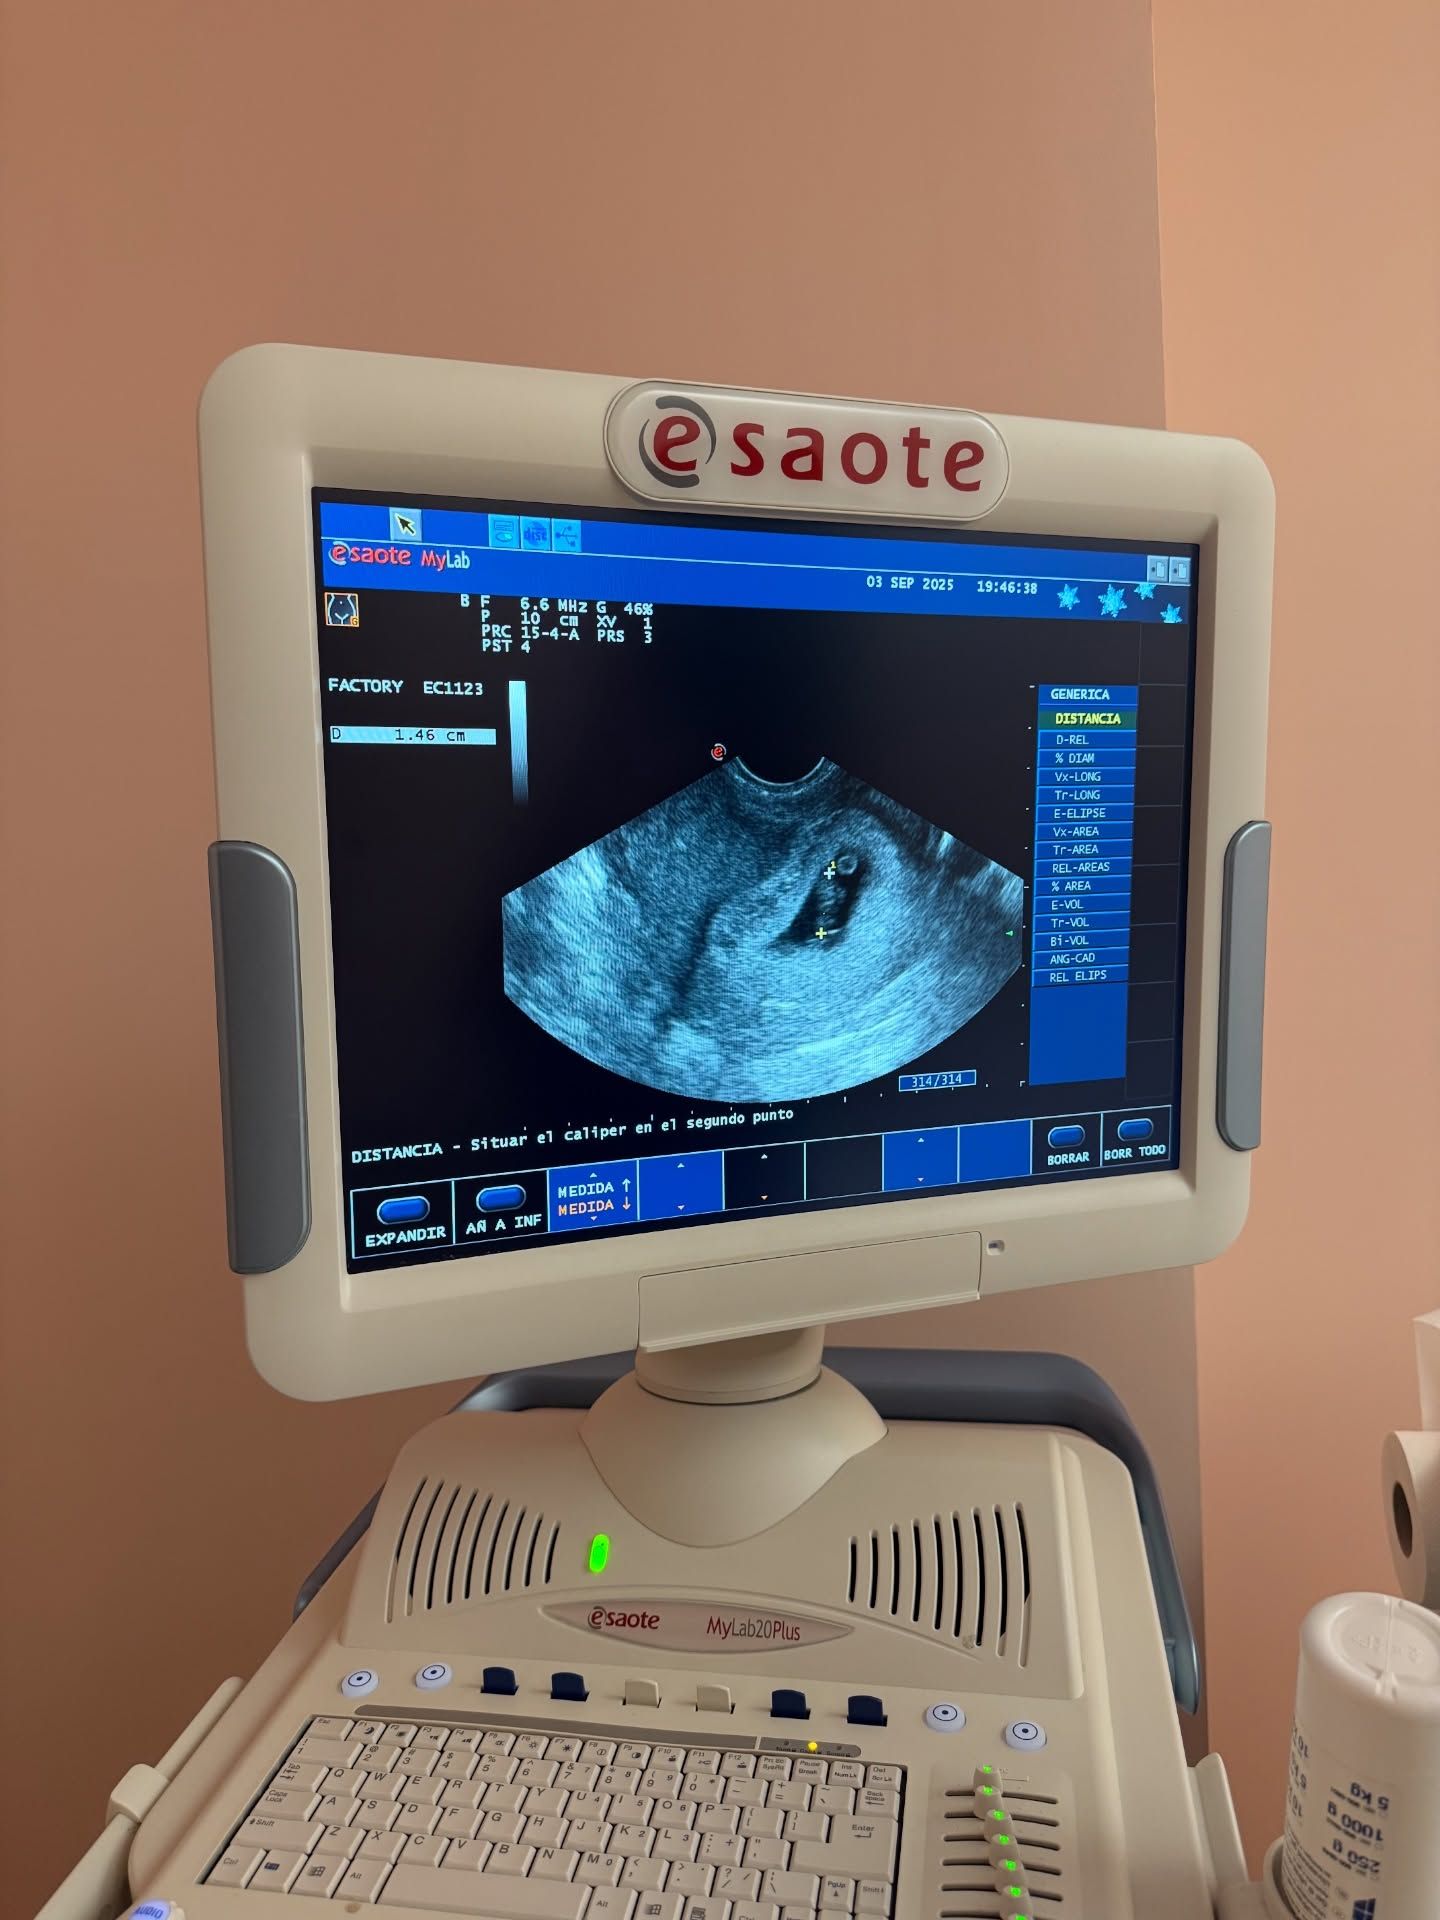

¡¡¡¡Que voy a ser papá!!!!, grita el madrileño a través de Threads, la red social de mensajería instantánea de Instagram. Junto a este mensaje que el empresario comparte lleno de júbilo y con frenesí, se puede ver un ecógrafo. En la pantalla del mismo, las imágenes de un embrión de 1.46 cm de longitud.

Tal y como hemos podido confirmar desde Outdoor, esa medida corresponde a la longitud cráneo-rabadilla (CRL, por sus siglas en inglés), que se usa para estimar la edad gestacional. Un embrión de 1.5 CRL corresponde aproximadamente a unas 7 u 8 semanas de gestación. Teniendo en cuenta esto, que tal y como se puede ver en la pantalla del ecógrafo la eco fue realizada el pasado 3 de septiembre y que desde entonces han transcurrido 4 semanas, se estima que la exmujer de Fonsi Nieto se encuentre ahora de unas 12 semanas de gestación.